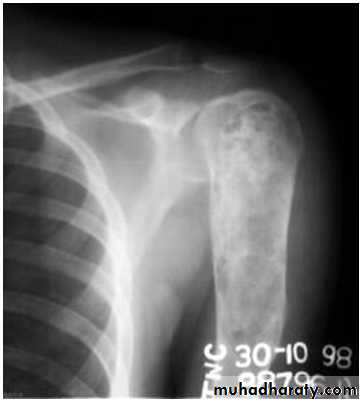

O/E vague swelling at the bone end and signs of joint irritation.X-ray:

Rarefied area of the bone end reaching just below the articular surface.Eccentric lesion with bone expansion and ballooning with cortical thinning, sometimes pathological fracture.

There may be calcific trabiculations inside the lesion giving it the commonly known saop-bubble appearance.